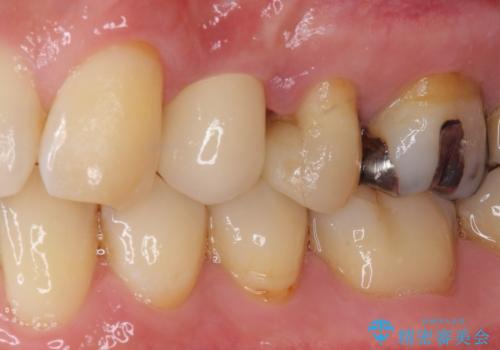

ジルコニアカスタムアバットメントは、歯肉ラインに金属が見えにくいというだけでなく、クラウンを装着する土台の形が天然歯と近い形態となるため、清掃性が高く歯肉が腫れにくいというメリットがあります。

インプラントは、人工骨を用いた際の骨誘導能が比較的高いとさせるストローマン社のSLActiveを使用しました。